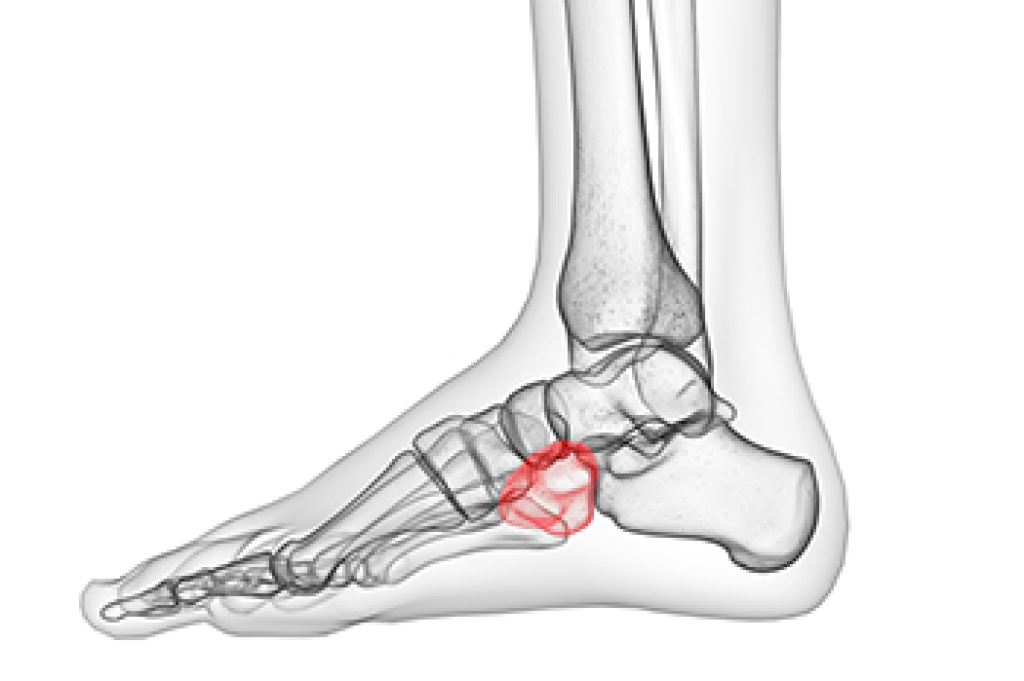

Cuboid syndrome occurs when the cuboid bone in the foot becomes partially dislocated or misaligned, leading to pain and discomfort. This bone is located on the outer side of the foot, and misalignment can result from repetitive stress, ankle sprains, or sudden twisting motions. Common symptoms include pain on the outside of the foot, difficulty walking, and a feeling of instability when standing. The pain may worsen with physical activity or pressure exerted on the foot. Diagnosing cuboid syndrome often involves a physical examination by a podiatrist, who may manipulate the foot to check for tenderness or abnormal movement of the cuboid bone. X-rays or other imaging tests may also be used to rule out other conditions and confirm the diagnosis. If you have pain on the outside of your foot, it is suggested that you consult a podiatrist who can determine the cause and provide treatment.

Cuboid syndrome is a common cause of lateral foot pain, which is pain on the outside of the foot. The condition may happen suddenly due to an ankle sprain, or it may develop slowly overtime from repetitive tension through the bone and surrounding structures.